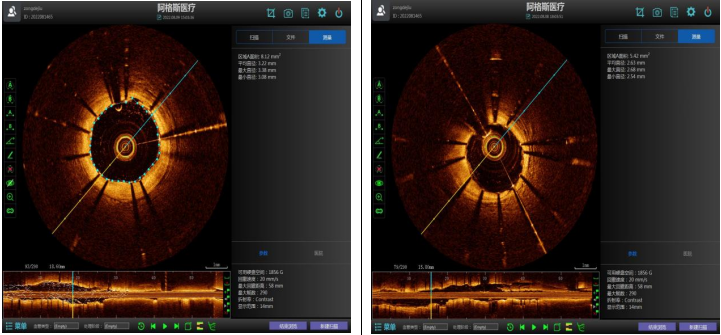

术中,手术团队通过新一代国产光学相干断层(OCT)检查,可直观识别到王先生前降支中段最狭窄病变处最小管腔面积在植入支架后由2.2mm²增至8.12mm²,支架全程贴壁良好,支架边缘未见夹层、血肿。

(支架植入后OCT检查提示支架贴壁良好)